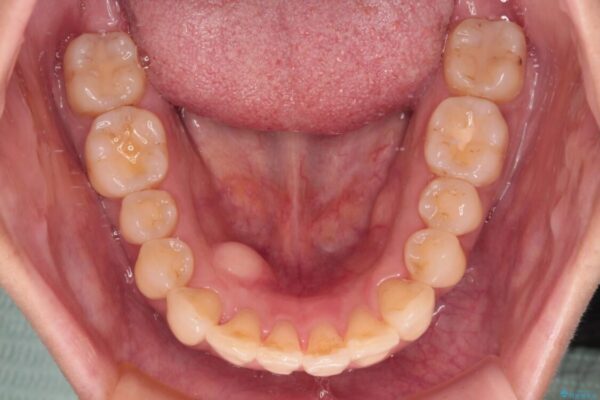

治療後

• インビザラインによる矯正治療と奥歯のインプラント治療 治療後画像

治療後について

歯の傾斜が改善され、インプラントによるクラウンが装着されたことで、物が挟まることもなくなりました。

左上第一大臼歯を抜歯した際に、スペースを閉じたそうですが、歯が傾斜してものが挟まって不快とのことでした。

インビザライン矯正で全体の歯列と整えるとともに、左上第一大臼歯部にはスペースを作り、インプラントによる補綴治療を行うこととしました。